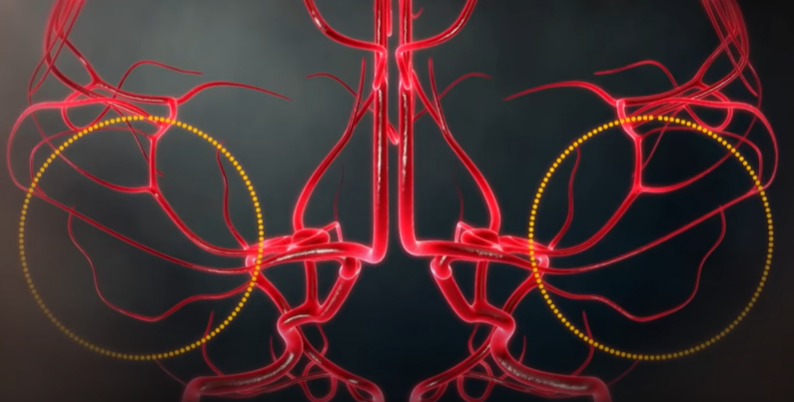

뇌동맥류 증상, 형태

아래 사진의 특정 환자의 경우, 모두 6개의 뇌동맥류가 자리 잡고 있었다. 뇌동맥류는 터지기 전에는 별다른 증상이 없지만 크기가 클 경우 두통을 일으키기도 한다.

뇌동맥류의 크기가 가장 중요하다. 과거에는 10mm 이상의 뇌동맥류를 큰 동맥류라 했는데, 지금은 가장 긴 직경이 7mm 이상 되는 크기면 위험하다고 한다. 또한, 모양도 중요한데 밋밋하고 평평하게 생긴 뇌동맥류는 파열 위험성이 적으나, 매끈한 표면이 아닌 불룩한 형태의 울퉁불퉁한 형태나 뾰족한 뇌동맥류는 위험할 수 있다. 혈압이 높거나, 흠 연하는 경우, 여성이나 고령의 환자는 뇌동맥류가 커질 확률이 크다.

- 신경외과 김종수 교수